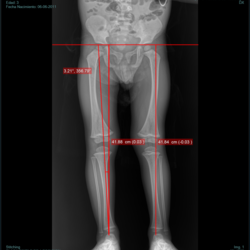

Eje mecánico